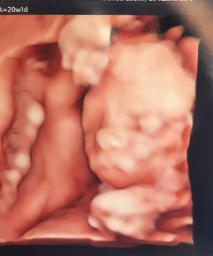

aneta wrote:Cześć dziewczyny, u mnie już po prenatalnych, na szczęście wszystko dobrze wyszło, fajnie było zobaczyć znowu malutką po tak długim czasie 🥰

https://zapodaj.net/plik-dyJzVCTx1v

Aneta, ale piękne zdjęcie 😍 to jest 4d??? ja miałam robione 3D na 1szych prenatalnych, ale dzidzia wyglądała jak kosmitka haha